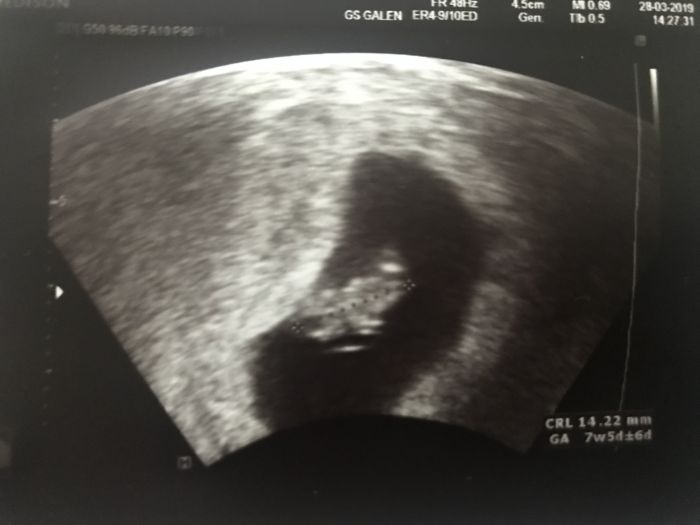

Ahoj holky,tak už i my máme foto z UTZ. Dnes jsem viděla jak bije srdíčko :) Další kontrolu mám 18.4.